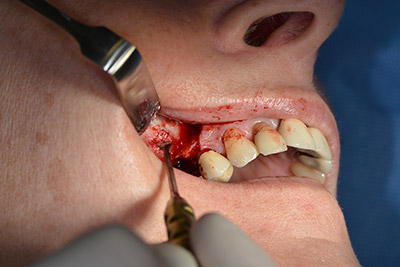

Имплантът е поставен и костта е изградена. В този случай, поради големината на зоната за аугментация, автогенните костни парченца, събрани с костен сондаж след имплантирането в зона 16 и фенестрацията в зона 14, са смесени с костозаместващ материал.

Използвана е абсорбираща мембрана като бариера на букалната страна и покритие на аугментацията. Накрая са поставени устойчиви на слюнка конци (Фиг. 15 до 19).

Аугментация с автогенна кост

Снимка 15

Снимка 16